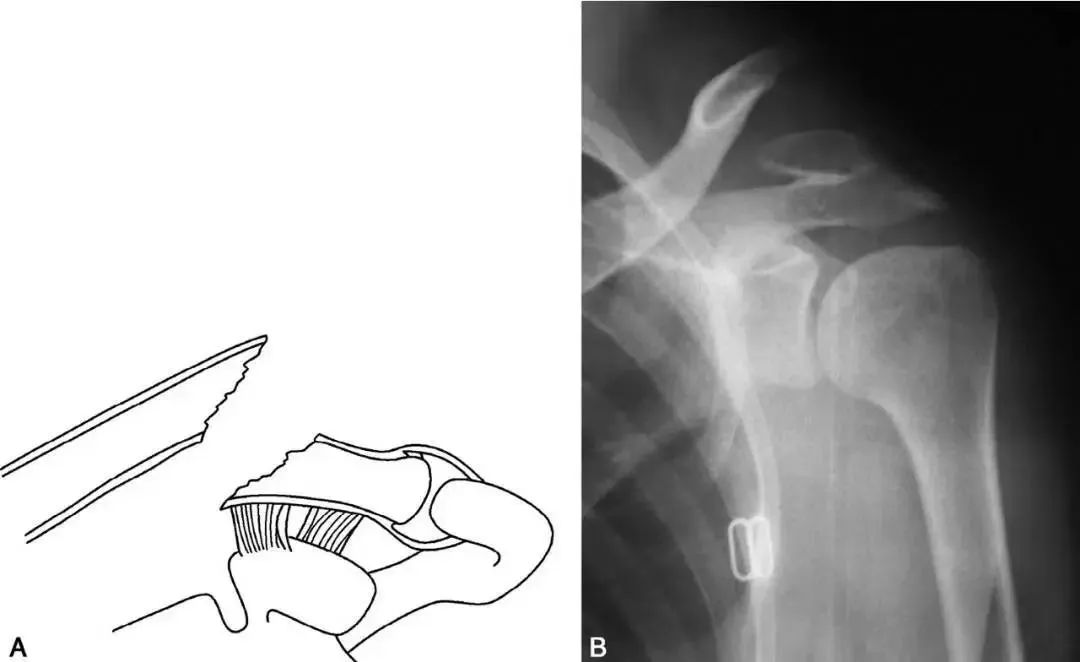

Ⅱ型(外1/3骨折)

對(duì)于大多數(shù)不穩(wěn)定骨折,目前大多數(shù)學(xué)者認(rèn)為,除了功能要求較低和不能耐受手術(shù)的老年患者外,均建議早期行手術(shù)治療。目前已有很多內(nèi)固定技術(shù)用于治療鎖骨遠(yuǎn)端骨折,例如克氏針固定、喙鎖螺釘固定、鎖骨遠(yuǎn)端鎖定鋼板及鎖骨鋼板鉤等。